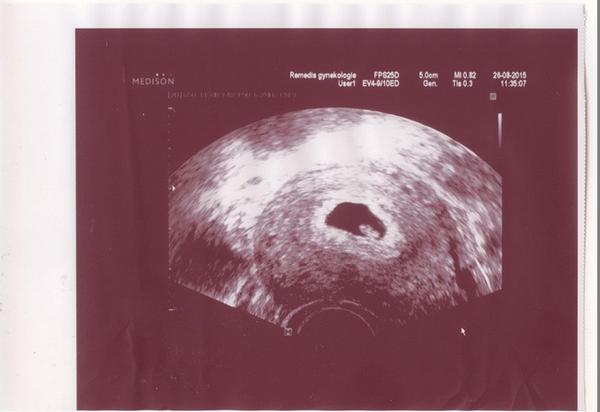

No jinak jsem v 7tt, srdíčko máme, prcek v pohodě a já po ránu totálně nepoužitelná 😀 Za týden jdu na kontrolu,tak snad už bude větší a vše bude v pohodě 🙂 Přikládám fotku krásné čmouhy ve čmouze 😀